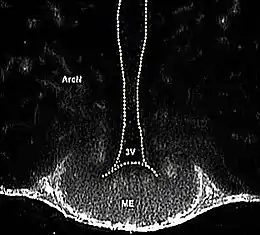

![]() ME= Eminencia media. 3V= tercer ventrículo. | ||

La eminencia media (ME en inglés) es una franja estrecha de tejido, comprendida entre el suelo del tercer ventrículo por arriba y la pars tuberalis de la adenohipófisis por abajo.

La eminencia media forma la pared inferior y el piso del tercer ventrículo.[2]

En un corte de plano frontal (transversal) del cerebro, la EM se ve como una franja estrecha de tejido nervioso, comprendida entre el suelo del tercer ventrículo por arriba y la pars tuberalis de la cual arranca el infundíbulo y la adenohipófisis por abajo.[6] [3]